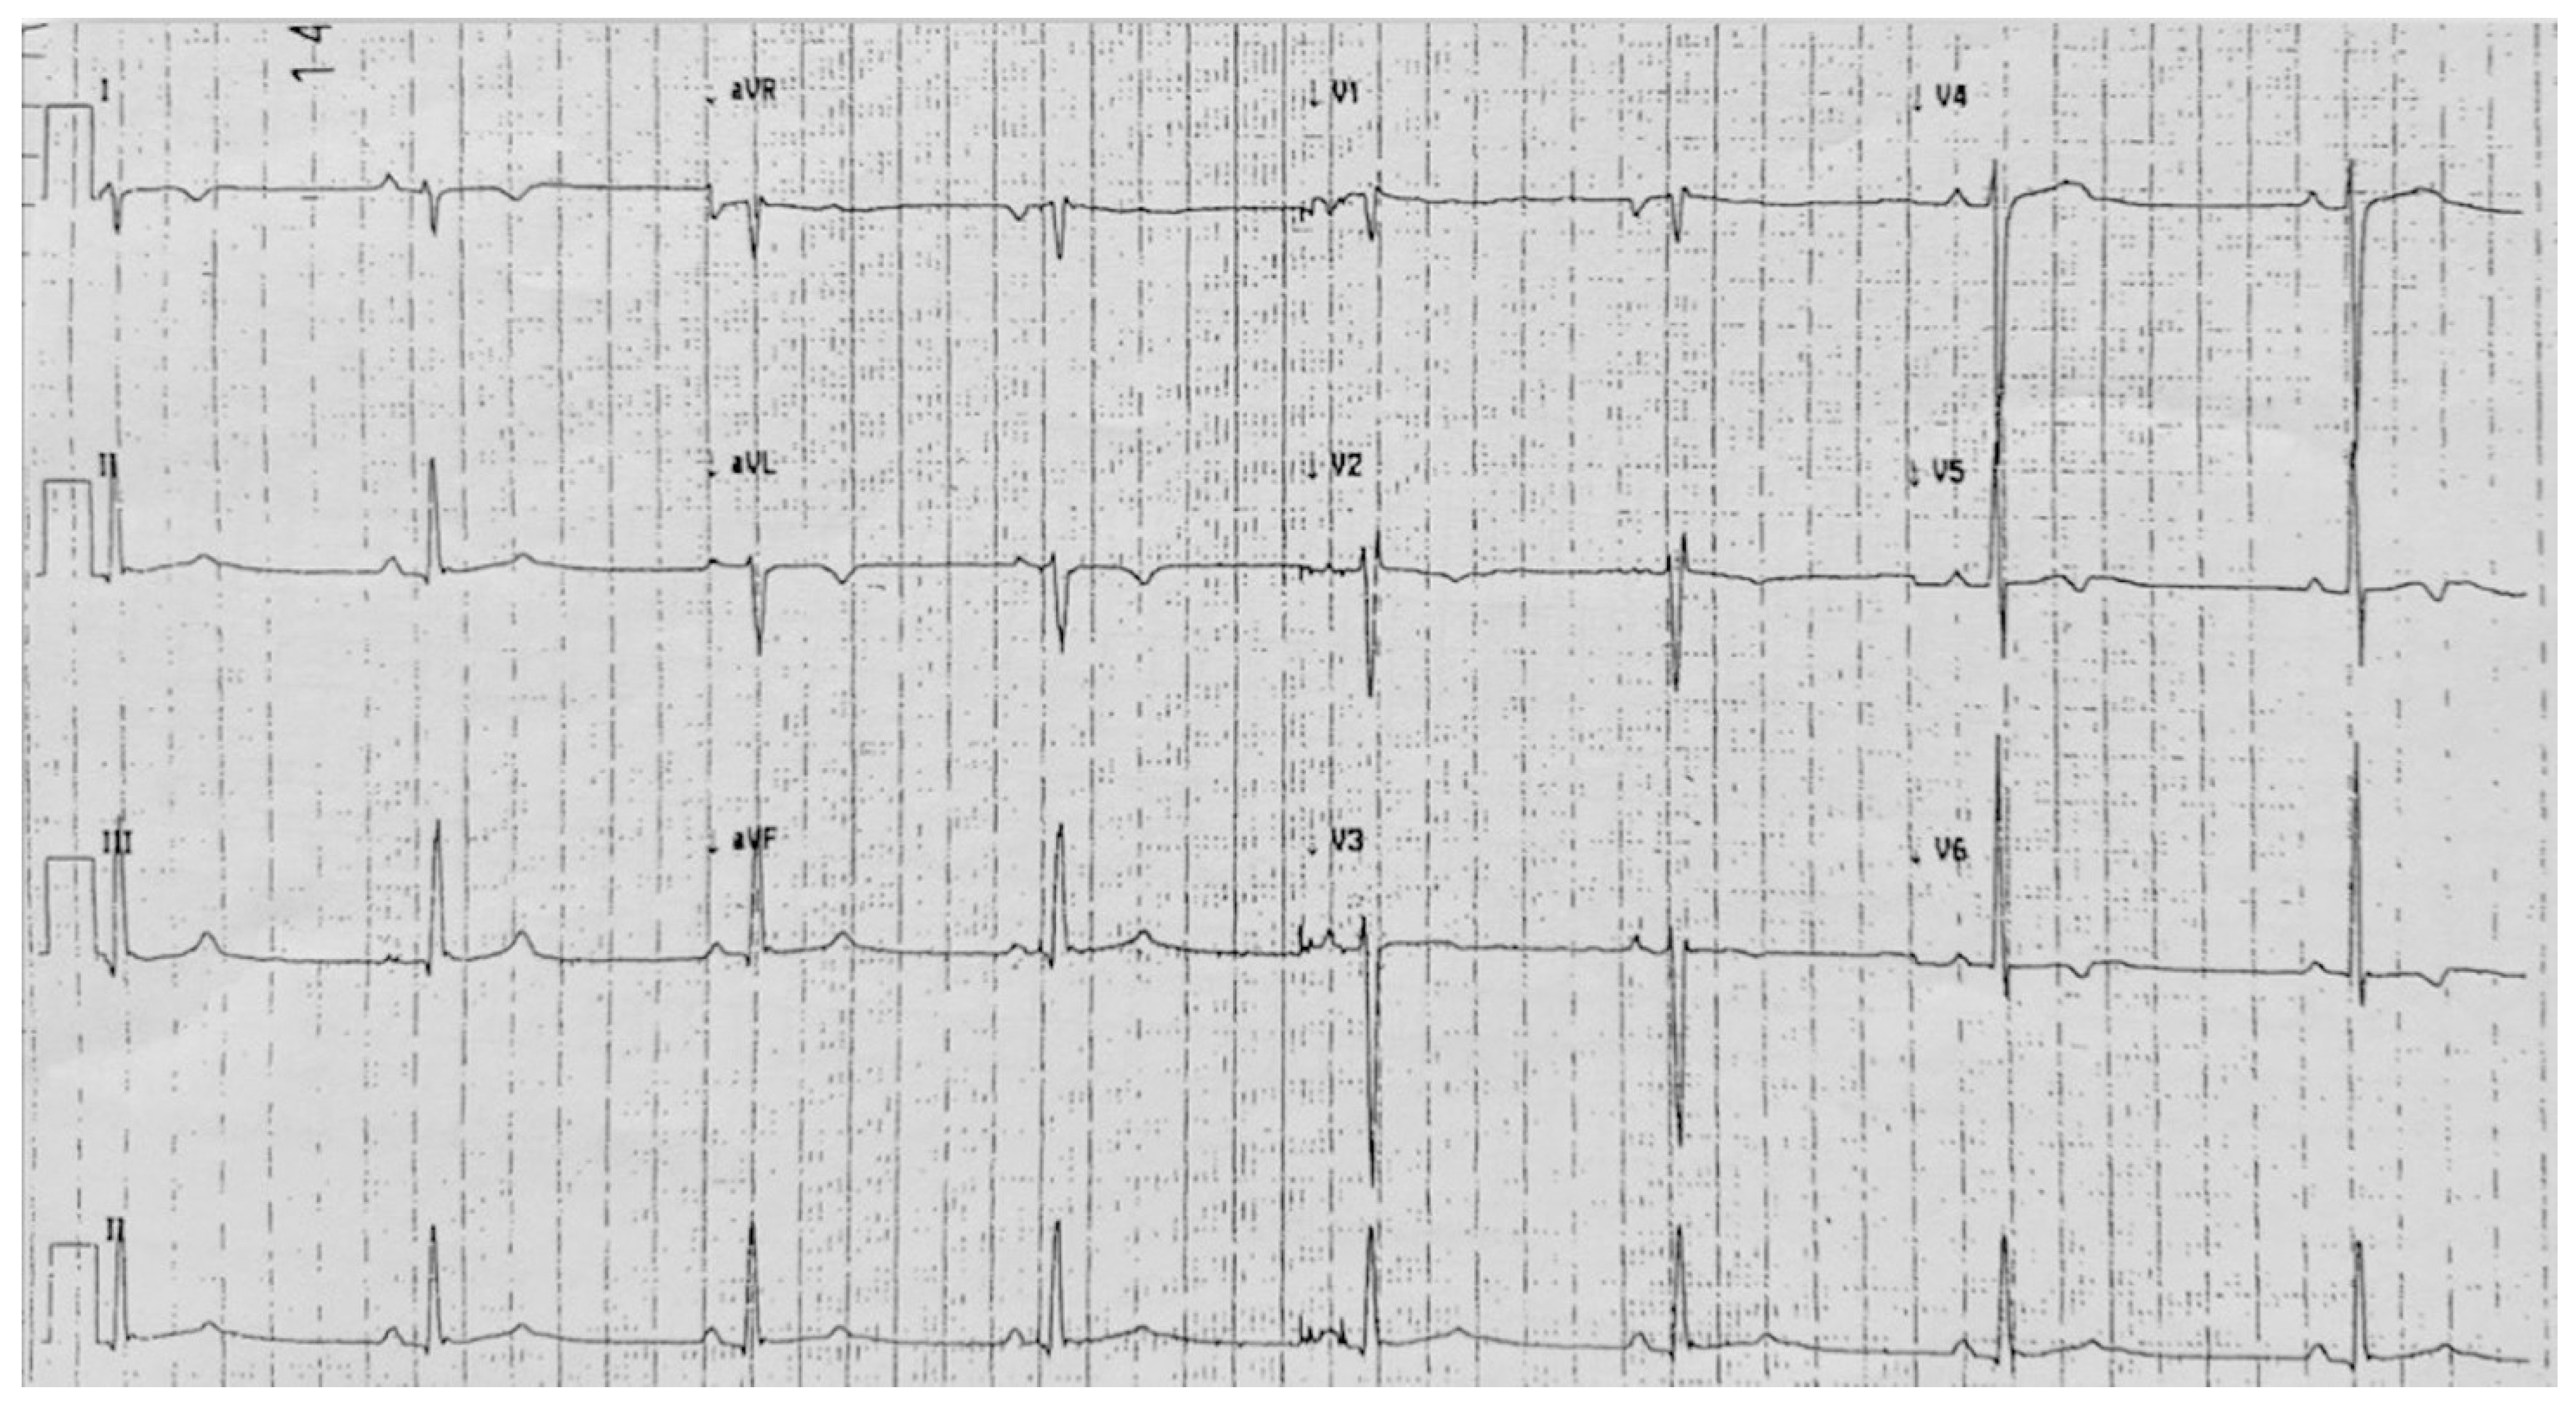

4. Case 3